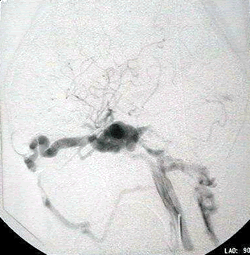

3.如需要了解血供情況,可選擇磁共振血管造影。

腦膨出顱周竇或血管瘤與顱內靜脈竇交通,隨頭部位置的改變腫塊大小變化明顯,穿刺可抽到血液,注入造影劑可能使顱內靜脈竇顯影。